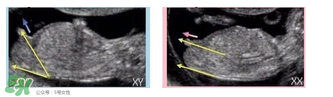

必須要NT超圖全景,可以看到下半部分的B超圖片才能判斷。外國人稱這種判斷法為nub theory。

主要通過尾椎那里判斷。 為了讓大家更直觀一些,我找兩個(gè)比較明顯的圖,男左女右,大家看男孩兒的特征點(diǎn)與身體呈45度角,還多一些,而女孩兒的特征點(diǎn)幾乎和軀體平行。圖第一張男寶,第二張女寶

用線條表示一下就更直觀了.當(dāng)然,這也不是完全絕對(duì)的,如果你們發(fā)現(xiàn)自己的寶貝兒與心想的不一樣,那這理論不一定對(duì),不是絕對(duì)的.千萬不要因?yàn)檫@個(gè)而影響自己孕期心情,寶寶健康是第一位的,我只是把自己所了解到的知識(shí)給大家普及一下。